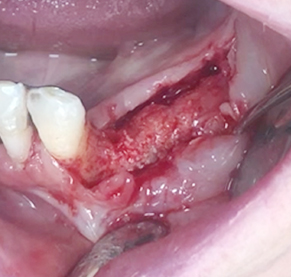

Implants/Bone Grafting

Partial edentulous clinical cases